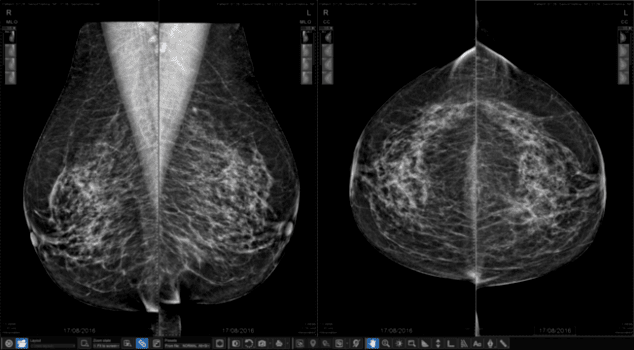

MAMOGRAFİ

Daha erken sıklıkla yapılan mamografi incelemesinin meme kanseri riskini artırdığını ve bu sürelere uymak gerektiğini unutmamak gerekir. Mamografi incelemesinde her iki memeden de ikişer adet çekim yapılır. Bir çekim süresi birkaç dakikayı geçmez. İnceleme için meme iki plaka arasında sıkıştırıldığı için hasta bir miktar ağrı hissedebilir. İnceleme tercihen adet bitiminden 2-3 gün sonrasında yapılır. Bu dönemde meme daha az ödemli olup hem daha az ağrıya yol açacaktır hem de tanısal değeri adet öncesi döneme oranla bir miktar daha iyi olacaktır.

Büyük kistleri olduğu bilinen ya da meme protezi olan hastalarda mamografi yapılmaz. Bu durumda mamografi yapılır ise meme kistlerinde patlama ya da meme protezinde hasar oluşabilir. Bu hastalarda meme ultrasonu dışında bir görüntüleme ihtiyacı olursa mamografi yerine meme MR tercih edilmelidir. Erken dönem meme kanserlerinde görülen mikrokalsfikasyonlar (milimetrik kireçlenmeler) en güzel bu inceleme ile saptanır. Bu nedenle mamografi ve meme ultrasonu birbirinin yerine yapılabilecek tetkikler değildir. Her ikisinin de avantajlı ve dezavantajlı özellikleri vardır. O nedenle taramalarda mamografi ve meme ultrasonunun birlikte yapılması uygun olacaktır.